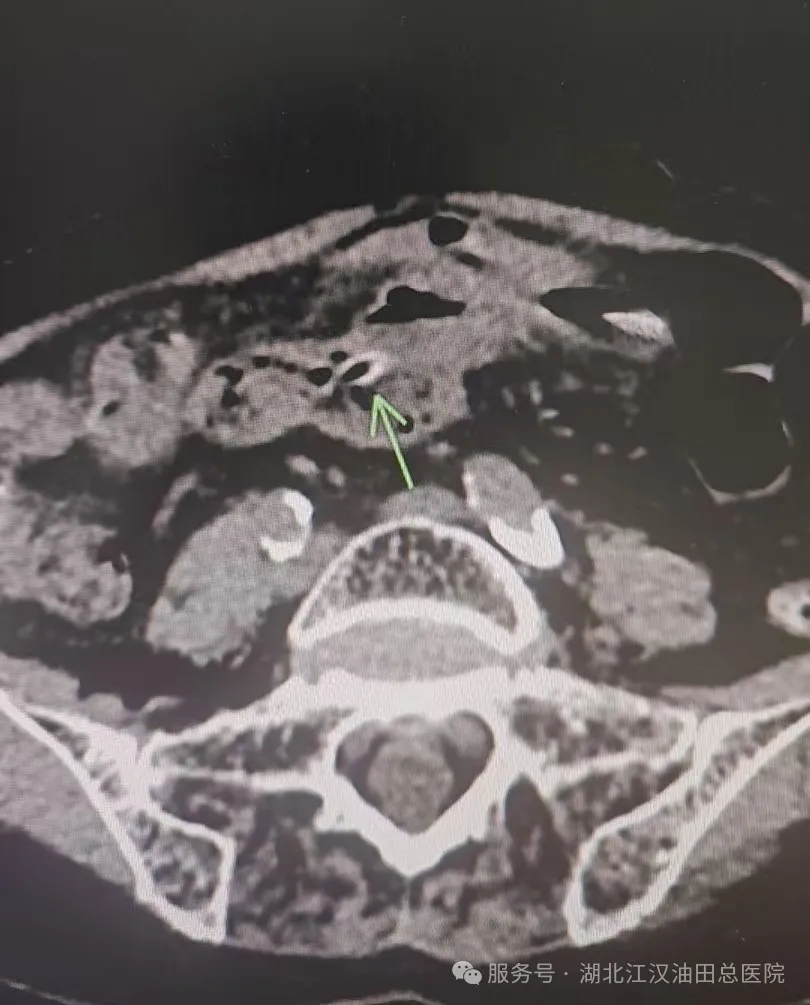

2月12号元宵夜,一位老年患者因右下腹痛急来我院就诊,经过我院普外科医生询问了解到患者近期食用过大枣,建议腹部CT检查,检查发现病因为异物刺破肠道引起穿孔伴腹膜炎,急诊手术也证实为枣核穿孔,术后恢复良好并顺利出院。这一案例为所有人敲响警钟:小小枣核,暗藏隐患,饮食安全切莫大意!

枣核图片